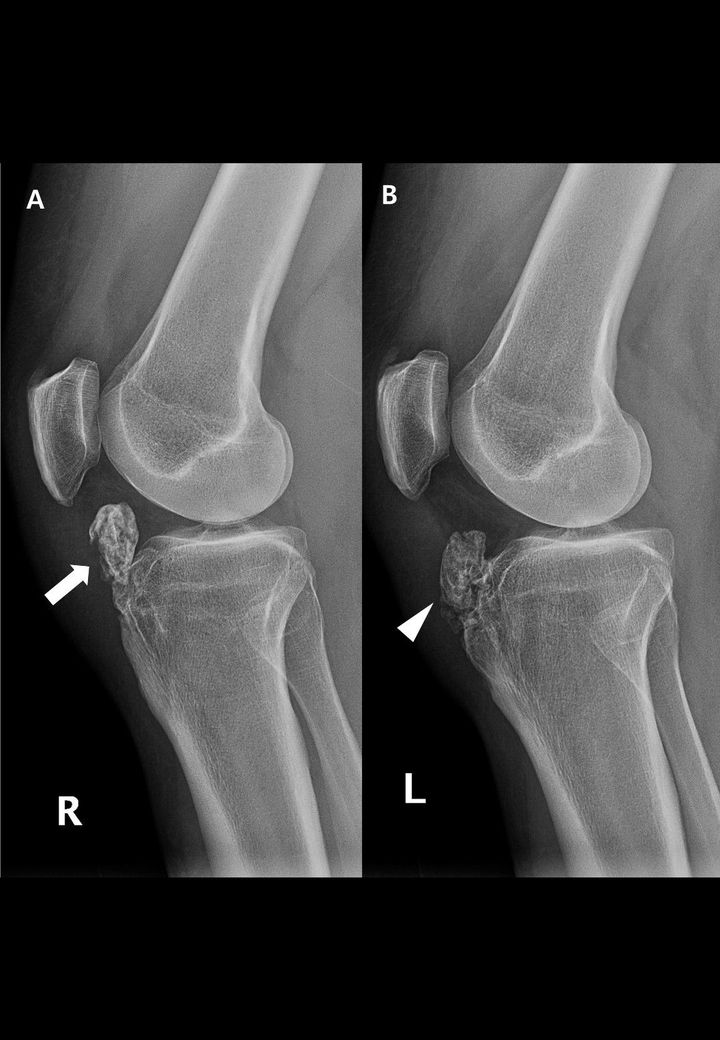

Diagnosis?

OSD with intra-articular large ossicle, in right knee large ossicle is beneath the patellar tendon and inside the infrapatellar fat pad.In left knee,it is partially fused with hypertrophied tibial tuberosity